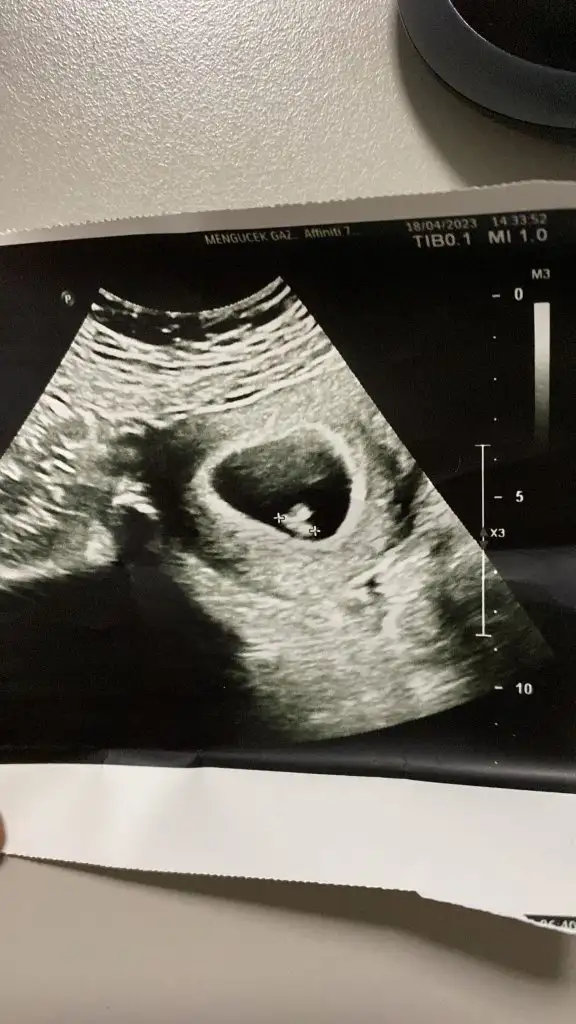

1ciftyesilgozz merhaba kizlar 8 haftalik olduk dun doktora gittik iki oglumdan sonra fikirlerinizi alayim varmi bizede bir tahmin